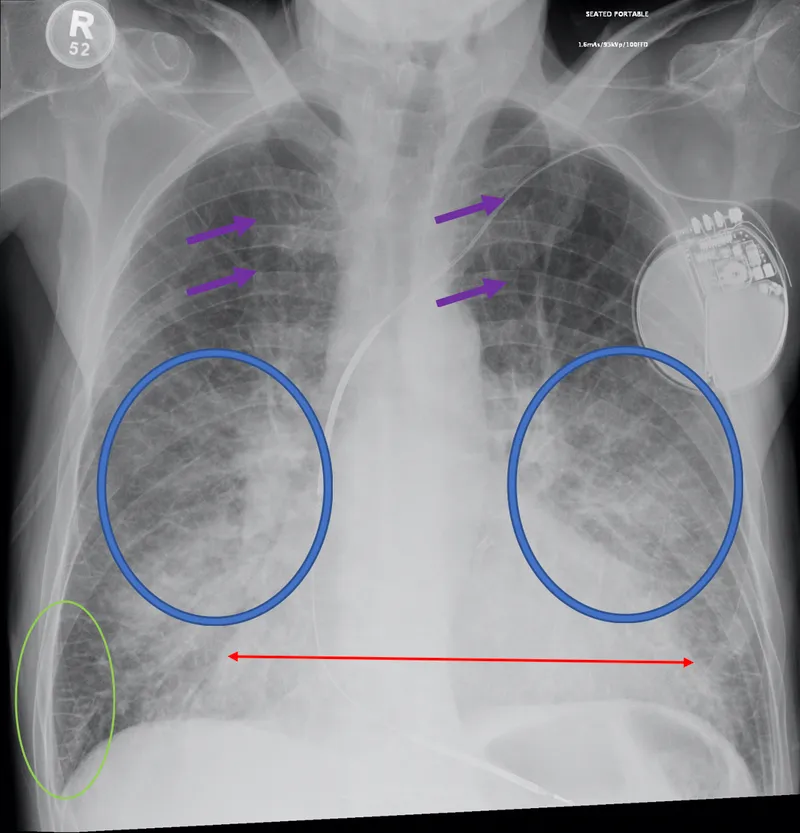

Pulmonary rales/crackles

| Bilateral rales | 70% | 78% | 3.2 | 0.38 | Moderate utility |